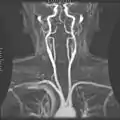

Angiograma por Resonancia Magnética.